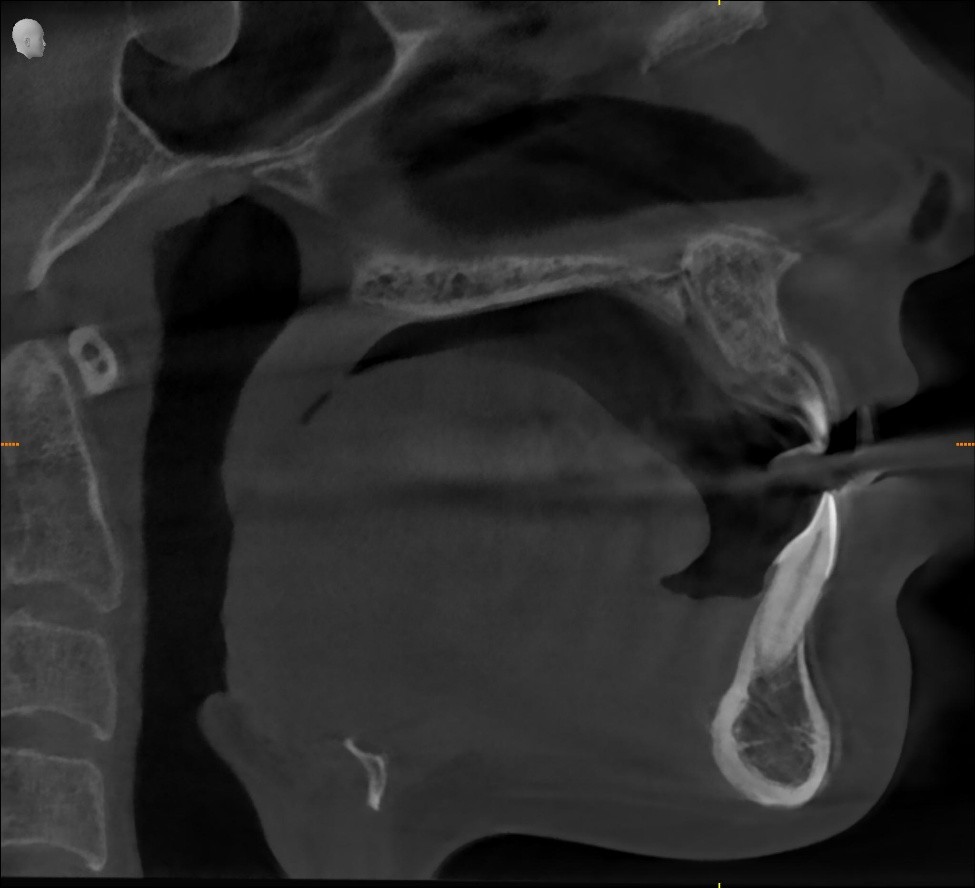

A detailed evaluation showed:

- Retruded lower jaw

- Low tongue posture

- Narrow upper arch

- Mouth breathing at rest

- Occasional snoring and sleep bruxism

A sleep and airway analysis confirmed:

▶ Partial nasal obstruction

▶ Narrow oropharyngeal space

▶ Early sleep-disordered breathing